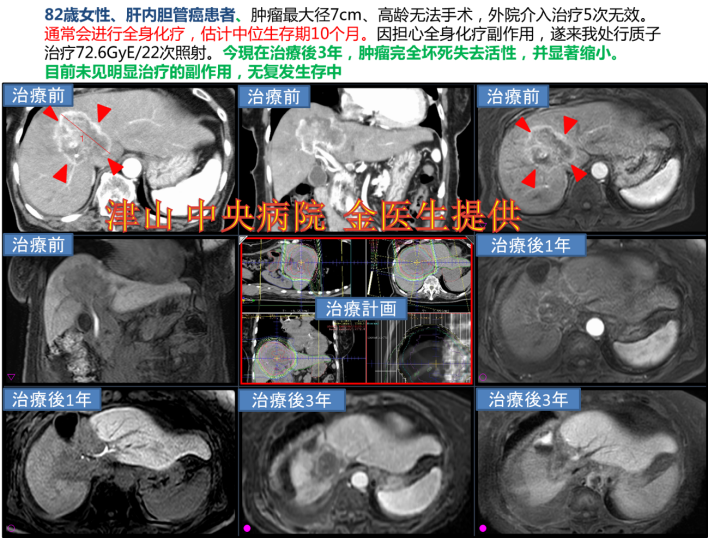

质子/重粒子的实际案例——肝内胆管癌(无法手术)

通过家属联系到我们,该患者又是高龄,又是无法手术切除干净的部位,经外科医生的建议,进行放疗。家属经过各方资料搜集,找到了质子重离子对正常组织伤害小,治疗期间无痛苦。满足了对患者的各方面需求并迅速办理医疗签证后来到了我们这里,赴日后不需要住院,患者和家属以旅游的心态,走遍各个城市,真正体会了疗养的慢生活。